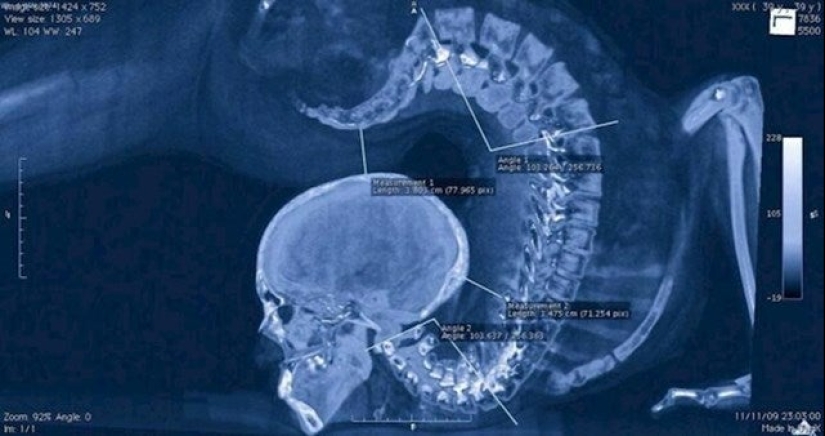

The body of a gymnast when performing a trick.